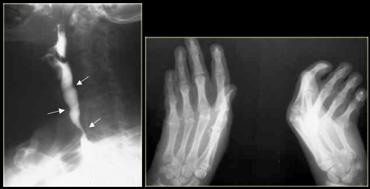

Bên trái là hình ảnh một bệnh nhân bị tụ máu thực quản.

Bệnh nhân nhập viện với triệu chứng đau ngực và khó nuốt sau khi nôn mửa.

Ngoài hình ảnh động mạch chủ ngoằn ngoèo, X-quang ngực bình thường.

Chụp thực quản barium cho thấy lòng thực quản hẹp (các mũi tên) trên phim thẳng và lòng thực quản dẹt trên phim nghiêng (các đầu mũi tên), gợi ý tụ máu trong thành thực quản.

Trên CT, chẩn đoán tụ máu trong thành thực quản được xác nhận.

Khối tụ máu thành thực quản tăng tỷ trọng (đầu mũi tên) được thấy cạnh ống thông mũi – dạ dày (mũi tên).

Sau điều trị bảo tồn, sáu tháng sau chụp thực quản barium cho kết quả bình thường.